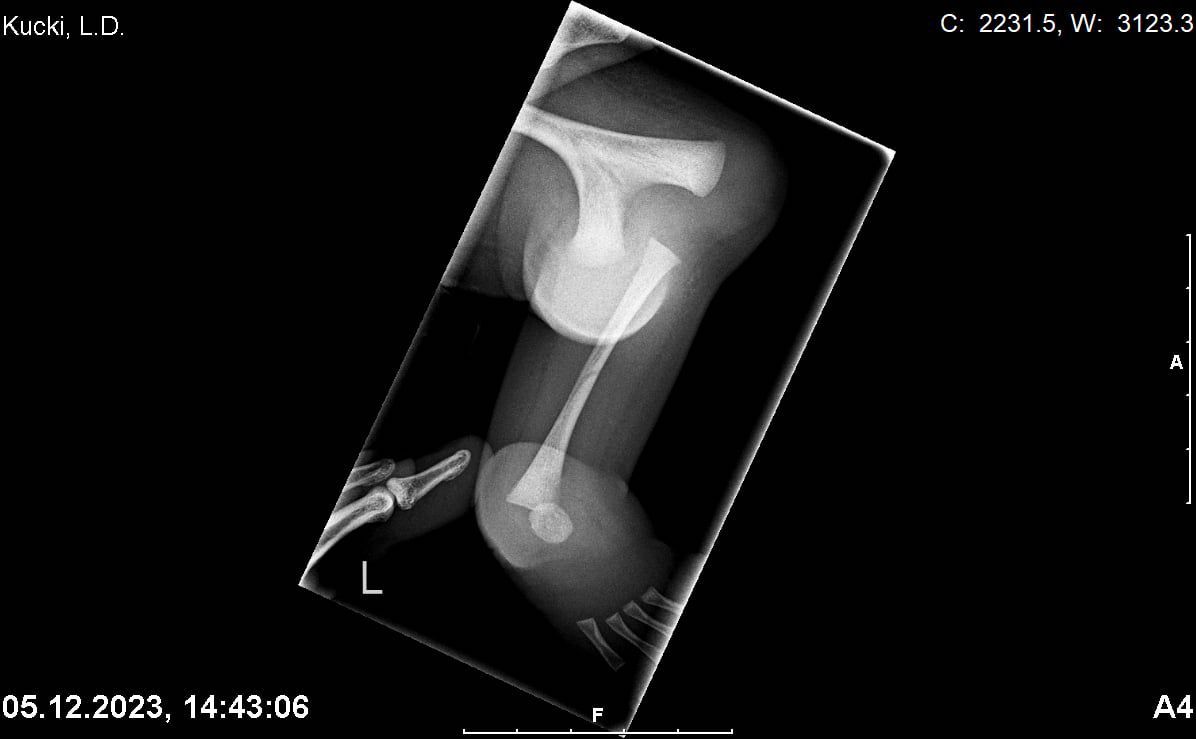

Po konsultacji z dr Paley – światowym ekspertem w dziedzinie ortopedii dziecięcej – poznaliśmy jego diagnozę i plan leczenia. Leo ma tylko jedną rzepkę oraz brak kości piszczelowej. Rodzice stanęli przed najtrudniejszą decyzją w swoim życiu.

Zdjęcia RTG nóżek po urodzeniu Leo